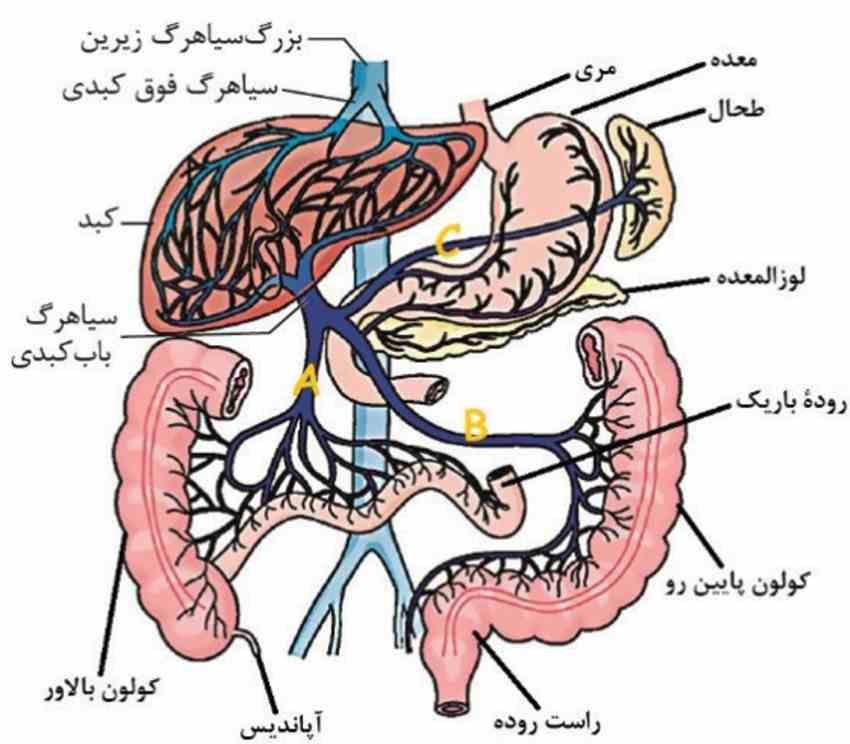

در سطح جلویی کلیه راست بخشی از کبد و کولون بالارو و در سطح جلویی کلیه چپ بخشی از لوزالمعده و کولون پایینرو قرار دارد.

۱-در کبد مویرگ خونی بین سیاهرگ باب وسیاهرگ فوق کبدی وجود دارد، یعنی بین دو سیاهرگ.